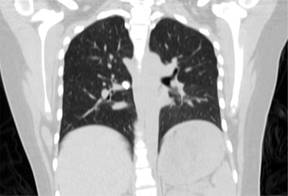

Se realiza gammagrama óseo con tecnecio 99 en Octubre de 2021, donde se observa incremento anormal de actividad osteoblástica en tercio medio de fémur. En TAC de tórax se encuentran metástasis paracardíaca derecha calcificada de aproximadamente 2 cm y metástasis periférica de 0.5 cm (Figura 2). En Octubre de 2021, se realiza segunda biopsia percutánea en quirófano, enviándose a patología, la cual reporta matriz extracelular amorfa con metaplasia ósea y escasa celularidad. Se realiza nueva valoración por el Servicio de Oncología Pediátrica, quien justifica, mediante resultado de biopsia, no cumplir con criterios para inicio de quimioterapia.

Figura 2: Tomografía axial computarizada inicial de la paciente, como parte de protocolo de estudio.